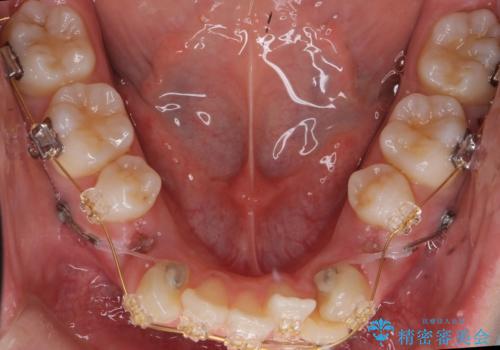

犬歯のコントロールが難しく、矯正用ミニスクリューを併用しました。

奥歯の歯の間が狭く、ミニスクリューを入れるのも難しい症例でした。

右上の前歯は変色もあり、神経の治療後にセラミックを被せる予定です。